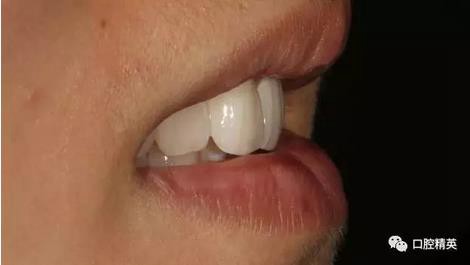

口內(nèi)正側(cè)位及切端特寫

從側(cè)位照可看出遠中切角略有回收